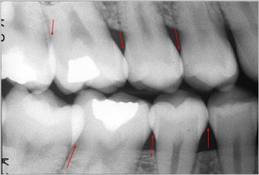

Radiografía de aleta mordible (Bite-Wing)

La técnica tiene ventajas con respecto a la radiografía periapical, debido que  reduce el tiempo de exposición a la radiación  y disminuye los costos y honorarios.

Técnica:

La cabeza del paciente se coloca de manera que el plano de oclusión quede paralelo al del piso. El rayo central se dirige al punto de contacto de los dientes superiores con los dientes inferiores y paralelo a sus superficies proximales, con el tubo formando un ángulo de 5 a 10º por encima del plano horizontal. Ver figura 5.

Para los dientes posteriores es deseable tomar dos vistas de cada lado:

• una en la que la película  se coloca más atrás para incluir el espacio inter-proximal  entre el segundo y el tercer molar,

• y la otra lo bastante adelante como para tomar la cara distal del canino. Solo necesita cuatro películas para el diagnóstico de caries en todos los sectores posteriores.

• Cuando el tercer molar se encuentra en proceso de erupción y se observa solo una parte de la corona clínica a la inspección visual, es de utilidad diagnóstica general, una imagen de una radiografía periapical de esa pieza dental en particular.

Figura 5